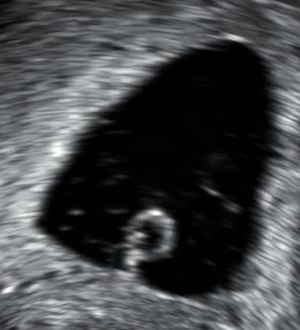

Transvaginal ultrasonography, with some products of conception in the cervix (to the left in the image) and remnants of a gestational sac by the fundus (to the right in the image), indicating an incomplete miscarriage

An incomplete miscarriage occurs when some products of conception have been passed, but some remains inside the uterus.[96] However, an increased distance between the uterine walls on transvaginal ultrasonography may also simply be an increased endometrial thickness and/or a polyp. The use of a Doppler ultrasound may be better in confirming the presence of significant retained products of conception in the uterine cavity.[97] In cases of uncertainty, ectopic pregnancy must be excluded using techniques like serial beta-hCG measurements.[97]